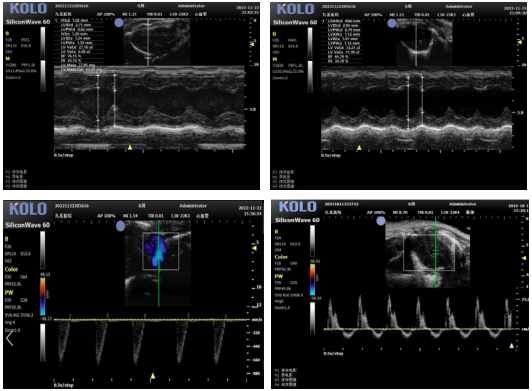

高分辨率小动物超声成像系统集成了全“芯”一代数据采集平台,采用超高频专用AFE芯片和独特的半导体CMUT探头,将图像的空间分辨率提升至30微米级高清成像。该系统配置大小鼠成像用超高频探头,丰富的软件测量包,便利的离线分析工作站和小动物专用操作平台,为开展大小鼠的心血管、腹部脏器、浅表组织等实验模型的影像学观察和数据分析提供了极大的便利性。

小动物超声系统专为活体、无创成像设计,适用于多领域研究。其配备的心电图、多普勒及B/M型超声技术,可实时评估心脏结构与功能,广泛用于心梗、心衰等心血管疾病模型。在血管研究中,能精确测量动脉管壁厚度,管腔面积,测量血管壁等。肿瘤研究方面,通过能量多普勒呈现肿瘤内微血管分布与血流,并可追踪肿瘤体积的动态生长。此外,系统亦支持对小动物腹部脏器进行持续监测与病灶追踪。该设备为心血管、肿瘤、代谢及脏器疾病的研究与药物评价提供了关键影像学工具。